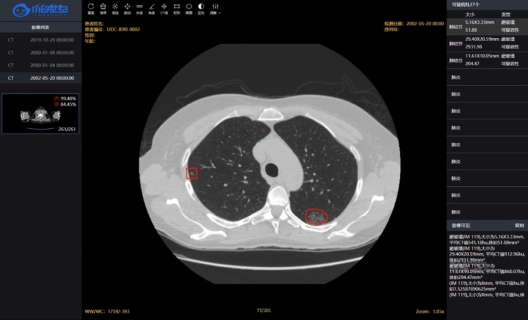

因此,国家呼吸系统疾病临床医学研究中心联合提供人工智能技术的北京小白世纪网络科技有限公司(简称“小白世纪”),针对新型冠状病毒肺炎,在原有全肺辅助诊断系统基础上,通过增加全国数千例新冠肺炎确诊患者肺部CT影像进行重新建模,成功研发了小白新冠影像AI辅助诊断系统。该系统采用小白世纪首席科学家黄高博士提出的新一代深度神经网络架构DenseNet(2017年)作为分割模型,融合SVM等机器学习方法,结合大量的临床数据,学习新冠肺炎的全部特征,在为患者诊断的过程中,计算机自动读取CT影像,利用该算法自动分析、对比,查找出与新冠肺炎相匹配的特征,从而达到快速、精准的诊断效果。目前,新冠影像AI辅助诊断系统已取得了有效应用。

小白世纪AI精准影像诊断系统